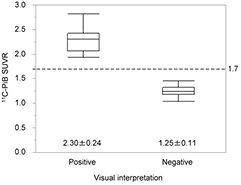

Amyloid PET is useful for early and/or differential diagnosis of Alzheimer's disease (AD). Quantification of amyloid deposition using PET has been employed to improve diagnosis and to monitor AD therapy, particularly in research. Although MRI is often used for segmentation of gray matter and for spatial normalization into standard Montreal Neurological Institute (MNI) space where region-of-interest (ROI) template is defined, 3D MRI is not always available in clinical practice. The purpose of this study was to examine the feasibility of PET-only amyloid quantification with an adaptive template and a pre-defined standard ROI template that has been empirically generated from typical cases. A total of 68 subjects who underwent brain 11C-PiB PET were examined. The 11C-PiB images were non-linearly spatially normalized to the standard MNI T1 atlas using the same transformation parameters of MRI-based normalization. The automatic-anatomical-labeling-ROI (AAL-ROI) template was applied to the PET images. All voxel values were normalized by the mean value of cerebellar cortex to generate the SUVR-scaled images. Eleven typical positive images and eight typical negative images were normalized and averaged, respectively, and were used as the positive and negative template. Positive and negative masks which consist of voxels with SUVR ⩾1.7 were extracted from both templates. Empirical PiB-prone ROI (EPP-ROI) was generated by subtracting the negative mask from the positive mask. The 11C-PiB image of each subject was non-rigidly normalized to the positive and negative template, respectively, and the one with higher cross-correlation was adopted. The EPP-ROI was then inversely transformed to individual PET images. We evaluated differences of SUVR between standard MRI-based method and PET-only method. We additionally evaluated whether the PET-only method would correctly categorize 11C-PiB scans as positive or negative. Significant correlation was observed between the SUVRs obtained with AAL-ROI and those with EPP-ROI when MRI-based normalization was used, the latter providing higher SUVR. When EPP-ROI was used, MRI-based method and PET-only method provided almost identical SUVR. All 11C-PiB scans were correctly categorized into positive and negative using a cutoff value of 1.7 as compared to visual interpretation. The 11C-PiB SUVR were 2.30 ± 0.24 and 1.25 ± 0.11 for the positive and negative images. PET-only amyloid quantification method with adaptive templates and EPP-ROI can provide accurate, robust and simple amyloid quantification without MRI.

Standard image High-resolution imageFigure 9 shows the results of 11C-PiB SUVR on the 2nd set of subjects obtained by PET-based EPP-ROI method. All subjects were correctly categorized into positive (n = 19) and negative (n = 15) using cutoff value of 1.7.

Figure 9. Box plots of 11C-PiB SUVR for positive and negative groups. All subjects were correctly categorized into positive and negative based on cutoff value of 1.7.

We tested the PET-only quantification method by applying it to a 11C-PiB image set acquired with two different PET cameras. As a result, all subjects were correctly categorized into positive and negative based on the cutoff value of 1.7. Categorization of 11C-PiB scans by the PET-only quantification method showed exact concordance with the visual read results. Therefore, the PET-only quantification method could help interpretation of amyloid images based on these results. This PET-only quantification method could be generalized to any other amyloid tracers if their specific templates are created, and the idea of standardizing the scaling of quantitative values may also be applicable (Klunk et al 2015).